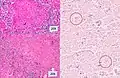

Gross pathology of the lung, spleen and kidney, showing micronodules (1–4 mm in diameter) which resemble millet seeds

Histopathology, showing epithelioid granulomas with multinucleated giant cells and acid-fast bacilli